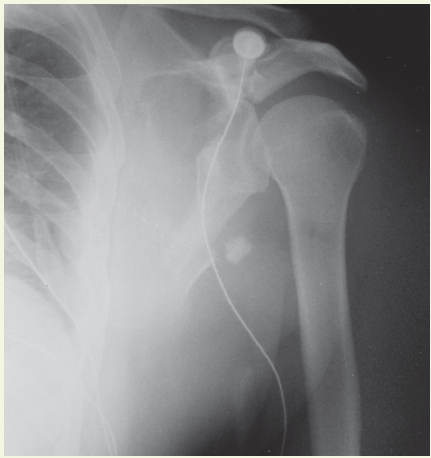

Bone fractures

04/27/2015

This article features a collection of photo-based cases demonstrating fracture-related issues, including Barton fractures, Psoas avulsion fractures, and orbital floor fractures.